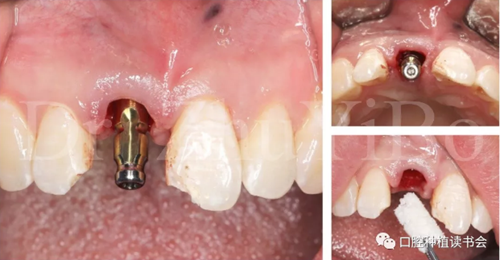

4.2.3 植入Nobel active種植系統(tǒng) RP 13mm種植體,植入扭矩大于45Ncm,初期穩(wěn)定性良好(圖11、圖12))。

圖11 使用Nobel active手用植入扳手精確控制植入方向

圖12 種植體初期穩(wěn)定性良好,注意與唇側骨板間的間隙

4.2.4取模,制作臨時修復體(圖13)。

圖13 一定要在植骨前,進行取模,有多種方法可以選擇

4.2.5 雙區(qū)植骨,戴牙(圖14,圖15)。

圖14 雙區(qū)植骨需要植到齦緣水平